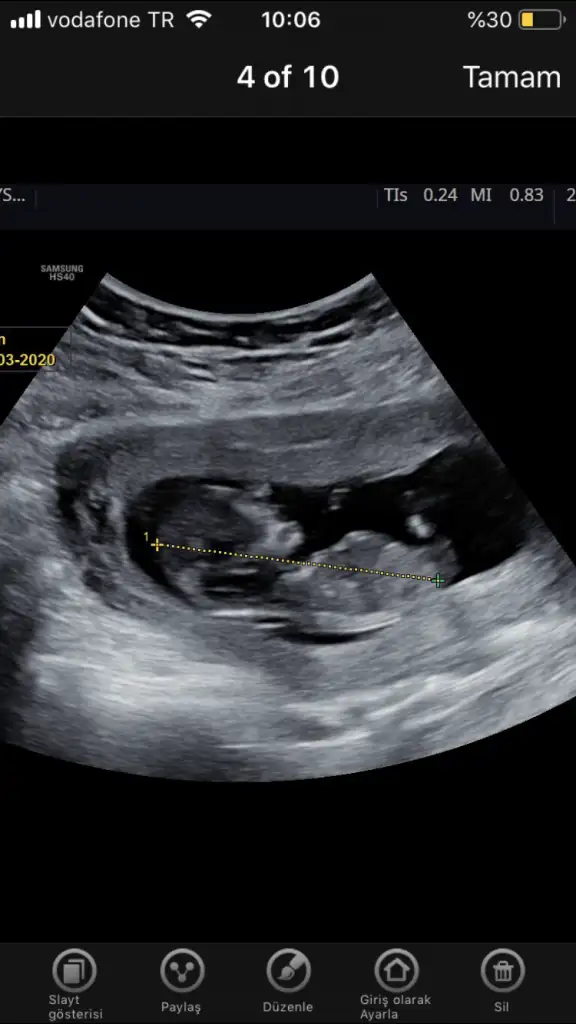

Kaç haftalık usg erkek diyorumBirde bu var net degil mi acaba

Kaç haftalık usg erkek diyorum

ErkekKızlar yeni görüntü 12+4 tahmin rica edebililirmiyim

Erkek gibiBirde bu var net degil mi acaba

Erkek gibi

Usg hic net degil cnm dr lar genelde bu haftalarda erkekse tahminde bulunuyorlar ama inan ben bisey goremedim icimden kiz demek gecti ama dedigim gibi usg ye gore tahmin degilSat 9+2 usgye gore 10 hftalik. Doktor kucuk bi tahminde bulundu. Siz de bi tahminde bulunurmusunuz